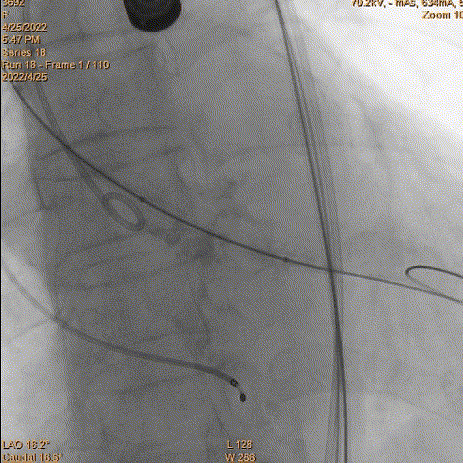

6、瓣膜回收和再释放:到达2/3后小弯侧较深,经多角度评估评估较深,起搏回收再次释放。

瓣膜再次释放

7、释放完成:第二次释放评估深度合适,缓慢释放脱钩,同轴性良好。撤递送系统,撤抓捕器。

二次评估深度

缓慢脱钩